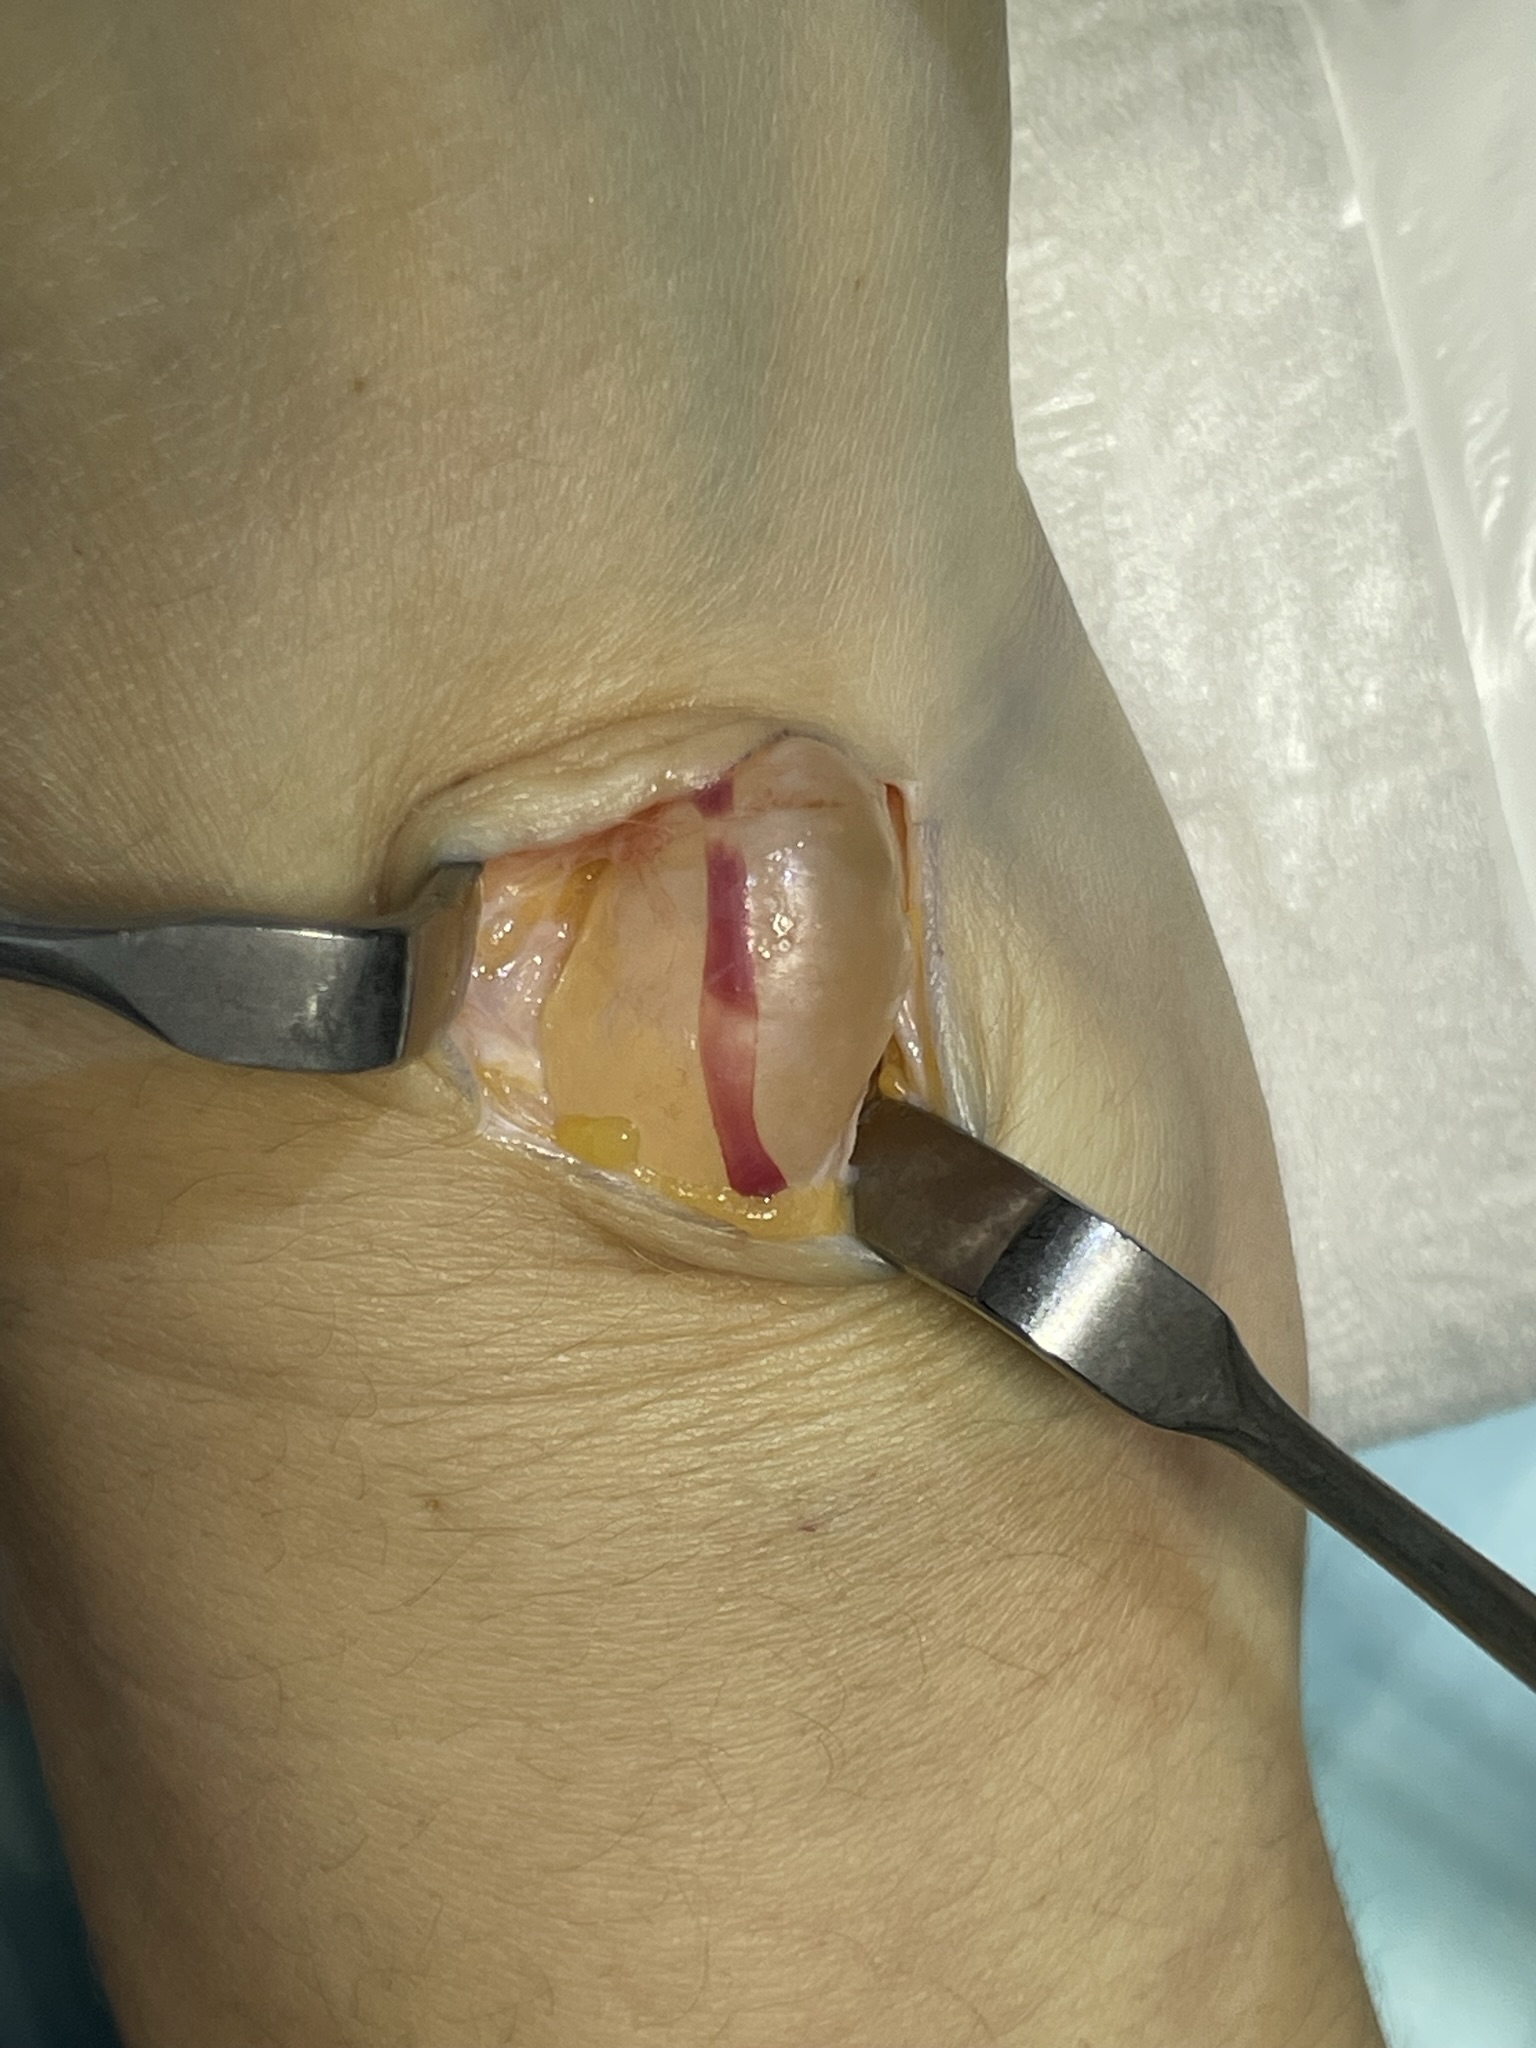

Клинический случай: тыльная гигрома запястья

Пациент с тыльной гигромой, подтверждённой на УЗИ. Выполнено хирургическое лечение, документированы этапы контроля и результаты.